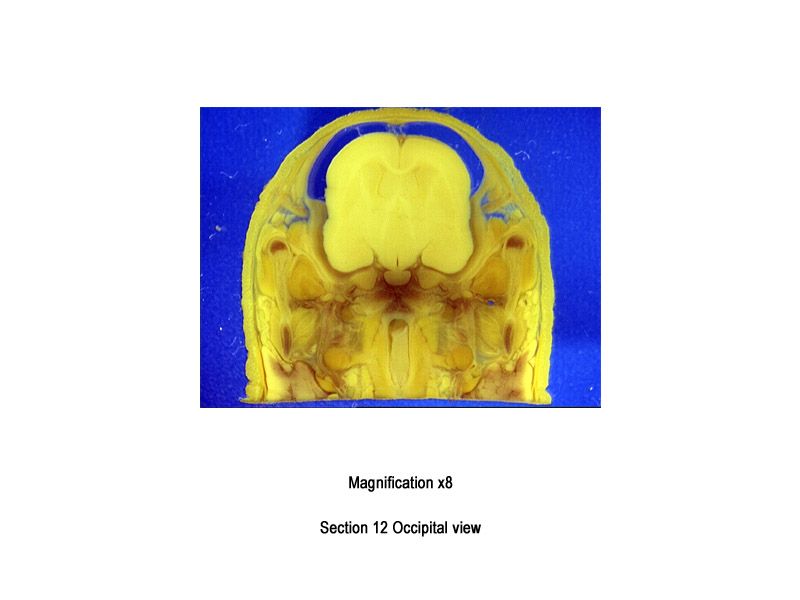

The images below show the normal appearance of Bouin's fluid fixed head sections in specimens at Day 29 of gestation (day mating observed = Day 0).

It is essential that both sides of each section is examined so that structures that exist is several sections can be visualised by the examiner in their mind as 3D.